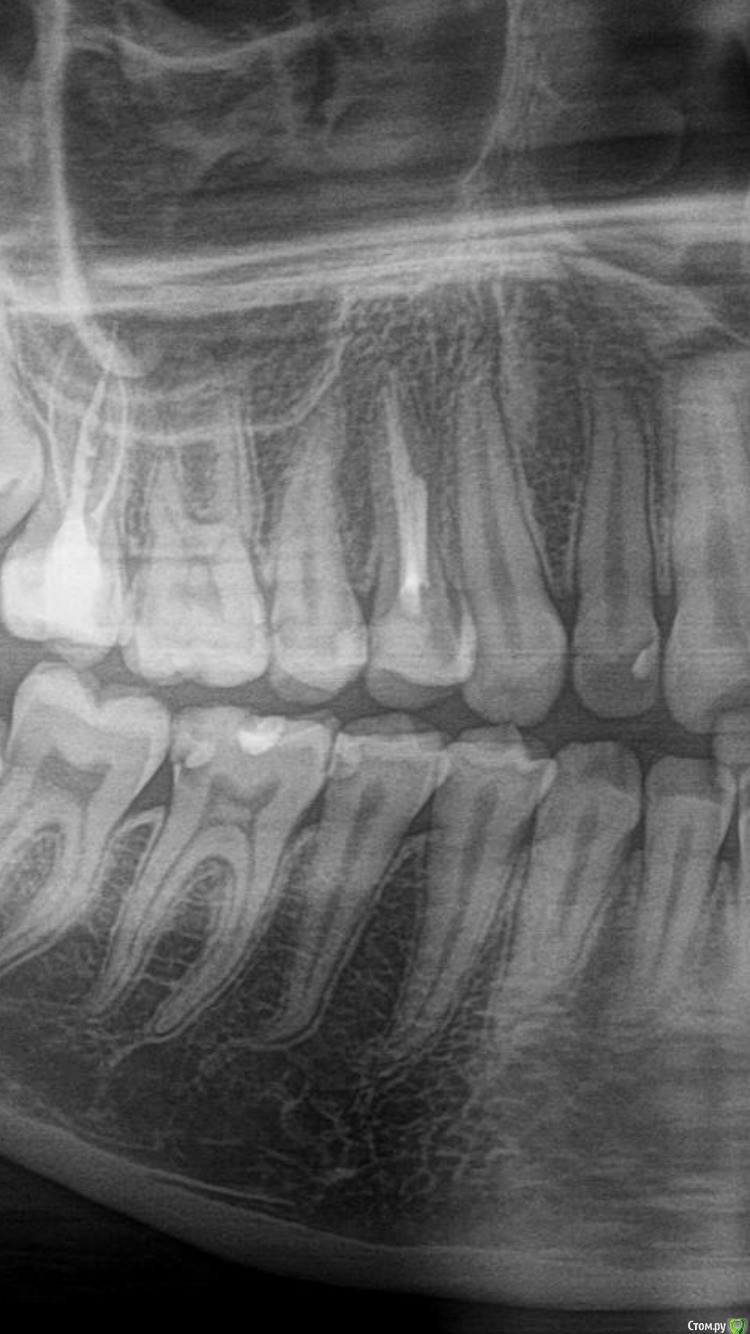

Marialalala Опубликовано 4 июня, 2020 Поделиться Опубликовано 4 июня, 2020 (изменено) Здравствуйте, лечу зубы, мой врач уходил в длительный отпуск, решила не терять время и сходила пролечила два зуба к врачу по отзывам в интернете. Принесла снимок этому врачу, он пролечил, зубы начали реагировать, я сходила сделала ещё снимок (в ближ.клинику), отправила этому врачу и описала жалобы, он сказал, что по снимку все хорошо, на мой вопрос о том, что за затемнение осталось в зубах, врач сказал, что это изолирующая прокладка, но я сразу скажу, что со слов врача и по акту оказания услуг мы лечили средний кариес, который разве предполагает изолирующую прокладку?. Врач сказал, что все хорошо, но если разболится, то приходите. Болеть вроде перестало, вышел с отпуска мой постоянный врач, мы начали лечить другие зубы, более насущные и как дошла очередь до этих зубов, он сразу по снимку сказал, что пролечено не до конца, необходимо переделать, при работе подтвердил, что мягкий дентин остался, в 6 зубе В одной точке вскрылась пульпа, но не кровила, врач решил пока не удалять нервы и поставил пломбу, с надёжной, что все будет хорошо. Я пишу тому врачу из интернета о том, что зубы он пролечил не качественно и хочу вернуть деньги, врач здоровается и пишет фио главрача и его данные. Главрач мне пишет о том, что почему вы не пришли на перелечивание, я говорю о том, что какое перелечивание, ваш врач сказал, что все пролечено хорошо! Главрач с меня просит новое ОПТГ (в той же проекции, разве у ОПТГ разные проекции?) и просит прислать чек и акт за работу во второе своей клинике, я сначала согласилась, а потом посоветовалась с подругой юристом, которая сказала, чтобы я писала досудебную претензию и без всякий новый снимков и чеков со второе клиники, ведь есть снимок после их врача по которому все и так понятно. Как мне быть? Есть ещё такой момент, что своего постоянно врача я не хочу в это втягивать, писать им координаты клиникИ и т д, ну вот не хочу, я же имею на это право? Что мне делать, как всё-таки вернуть с них деньги? Снимки до лечения и после лечения временного врача прилагаю (разница в снимках пару месяцев). 46 и 45 зубы! Изменено 4 июня, 2020 пользователем Marialalala Ссылка на комментарий